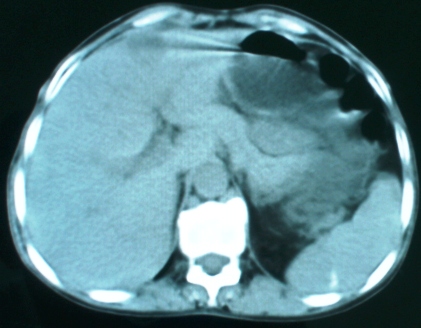

以下是引用zsl6918在2008-11-4 19:14:00的发言:[br]多发转移性改变,子宫改变不除外为原发灶